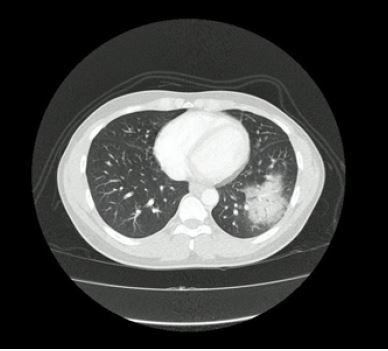

El caso corresponde a un hombre de 34 años de edad, natural de Valledupar y procedente de Bogotá, con diagnóstico de infección por VIH estadio 3 con adecuado control inmunovirológico, quien acudió al servicio de urgencias con un cuadro clínico de 4 días de evolución, caracterizado únicamente por singulto. No se encontraron datos positivos a la revisión por sistemas y no tenía otros antecedentes médicos relevantes. En el examen físico no se encontraron hallazgos significativos. Inicialmente, se manejó con haloperidol por vía intravenosa a una dosis de 2,5 mg cada 8 h durante 2 días, y posteriormente recibió metoclopramida a dosis de 10 mg por vía intravenosa cada 12 h durante 5 días sin presentar mejoría. Durante su estancia se registró un pico febril de 39 ºC. Dentro de los exámenes de extensión se evidenció leucocitosis y neutrofilia. La radiografía de tórax mostró una radiopacidad de ocupación alveolar en la base pulmonar izquierda en la proyección anteroposterior ( figura 1), también vista en la proyección lateral ( figura 2). Se consideró que el paciente se encontraba cursando una neumonía adquirida en comunidad, por lo cual se inició terapia antibiótica con ampicilina sulbactam y claritromicina. Sin embargo, ante un cuadro clínico poco claro, se decidió caracterizar el hallazgo radiológico mediante una tomografía de tórax de alta resolución, que confirmó que la ocupación alveolar se trataba de una consolidación ( figura 3). Tras 48 h de iniciada la terapia antibiótica, el singulto se resolvió. El informe final de los hemocultivos fue negativo y la evolución del paciente fue adecuada, por lo que se indicó egreso con control imagenológico en 6 semanas.